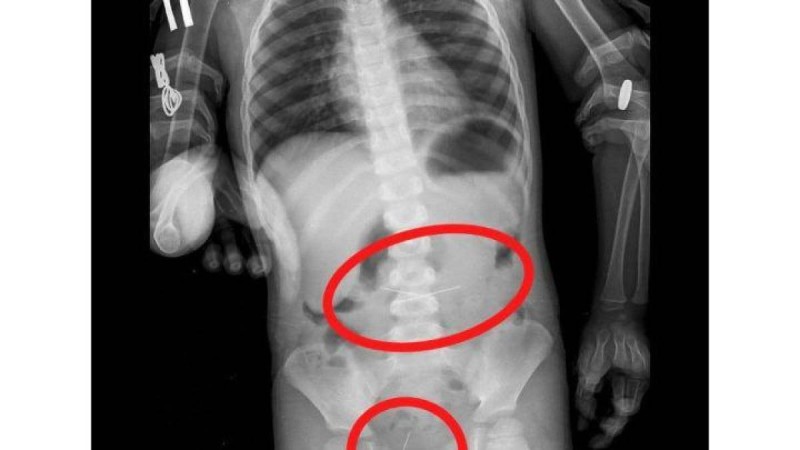

Үш жасар бала төрт тігін инесін жұтып қойған Дәрігерлер бірнеше тігін инелерін жұтып қойған үш жасар баланың өмірін сақтап қалды... 24 қаңтар 2023 • Шоу-бизнес